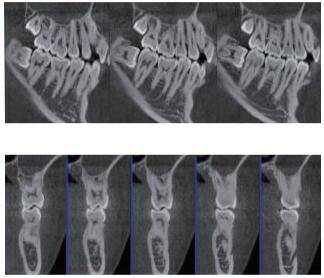

三維重建任意斷層

專(zhuān)有三維重建算法,可提供任意位置高清斷層影像。

多平面組合重建

可同時(shí)觀察軸向面、冠狀面和矢狀面圖像,方便臨床診斷。

口腔CBCT是一種新型的成像技術(shù),可應(yīng)用范圍包括多生牙、根充檢查,牙體牙髓及牙周檢查,種植術(shù)前診斷與設(shè)計(jì)等。如果您想采購(gòu)普愛(ài)醫(yī)療的口腔CBCT,歡迎聯(lián)系我們